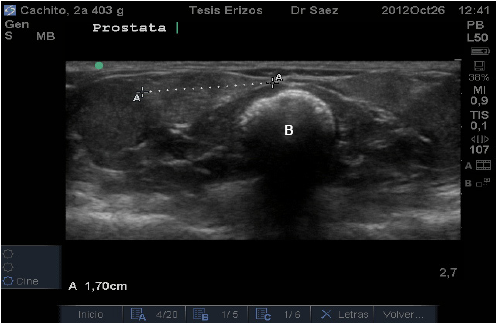

La próstata se localizó caudal a la vejiga, en un corte transverso fue posible visualizarla ventral al colon descendente y medial a cada testículo. En este corte, en cuatro individuos, cada lóbulo presentó una forma de “gota” con su eje mayor horizontal, siendo más redondeada lateralmente y fusiforme hacia medial (FIG. 8).

En el resto de los pacientes, se observó cada lóbulo de forma aplanada y alargada, teniendo la misma altura tanto medial como lateralmente, o si presentaban el extremo medial aguzado, éste era muy sutil (FIG. 9).

En el corte longitudinal presentó la misma forma, es decir, aquellos individuos que presentaron lóbulos prostáticos en forma de gota al corte transverso, la mantenían al corte longitudinal, siendo el extremo craneal el más redondeado y el extremo caudal más aguzado. Y aquellos individuos que presentaron forma aplanada al corte transverso, la mantenían al corte longitudinal. El órgano se observó con ecogenicidad media, de granulado fino y homogéneo.

En relación a la Próstata, llama la atención la diferencia de valores obtenidos para tamaño prostático entre individuos, llegando en algunos casos a bordear 1 cm, pudiéndose suponer una relación entre éstos valores y el peso del animal, sin embargo los resultados estadísticos de correlación demostraron relación baja entre las variables y no significativa (P˃0,05). Se puede inferir, por lo tanto, que el tamaño de la glándula no es constante entre individuos sanos, independiente de otras variables como el peso, lo que se debe tener presente para no cometer errores diagnósticos al evaluar este órgano.